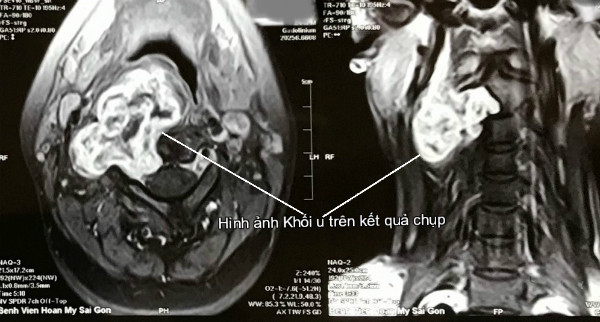

Bốn năm qua cô gái đi khám một số nơi nhưng chưa được chẩn đoán chính xác bệnh, chỉ cho kết quả là hạch cổ. Gần đây khối u to, tình trạng chuyển nặng nên bệnh nhân đến Bệnh viện Hoàn Mỹ Sài Gòn thăm khám. Kết quả chụp MRI cho thấy khối u bao dây thần kinh bên phải có đường kính 6 cm, xâm lấn thành họng bên phải.